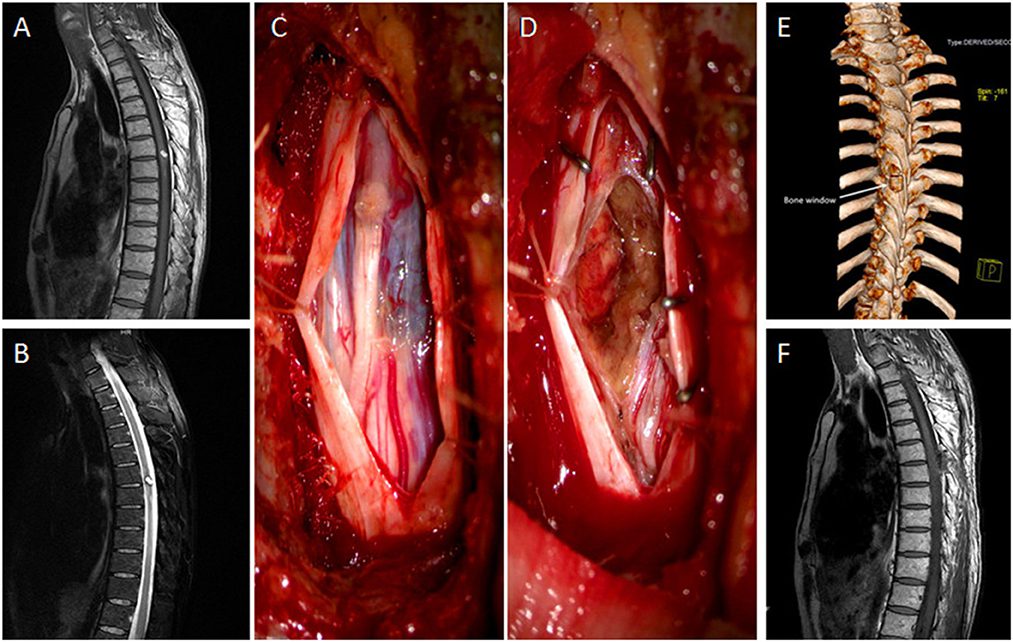

جراحی تومور نخاعی با هدف برداشتن توده و آزادسازی نخاع و اعصاب انجام می‌شود. این عمل معمولاً از طریق لامینکتومی یا میکروسکوپی انجام می‌شود تا جراح بتواند بدون آسیب به ساختارهای حساس، تومور را خارج کند. در برخی موارد، به دلیل محل پیچیده تومور، امکان برداشتن کامل آن وجود ندارد و بخشی از آن باقی می‌ماند که معمولاً با پرتودرمانی یا شیمی‌درمانی تکمیل می‌شود.

جراحی نخاع به دلیل حساسیت بالا نیازمند استفاده از تجهیزات پیشرفته و تیم تخصصی است. در طول عمل از پایش عصبی حین عمل استفاده می‌شود تا از بروز فلج یا آسیب عصبی جلوگیری شود.

روش‌های جراحی شامل برداشتن تومور و تثبیت ستون فقرات با پیچ و پلاک یا پروتز است. در برخی موارد، جراح از تکنیک‌های کم‌تهاجمی یا اندوسکوپی استفاده می‌کند تا دوره نقاهت کوتاه‌تر شود. در صورتی که تومور بدخیم باشد، درمان با پرتودرمانی و شیمی‌درمانی نیز ادامه پیدا می‌کند.